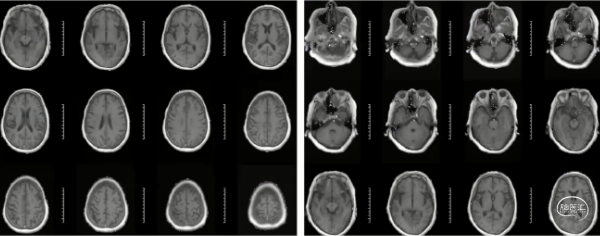

MRI (2023.06.25/本院)

右侧大脑半球梗死灶较前增加

MRI(2023.06.25/本院)

CTP(2023.06.26/本院):右侧额顶叶、半卵圆中心见片状灌注延迟区,TTP、MTT延长,CBF减低